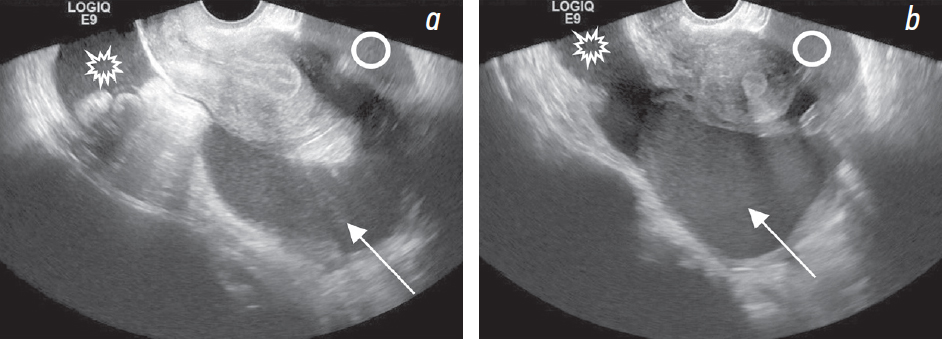

При КТ без внутривенного контрастирования выявлены свободная жидкость в полости таза, по боковым фланкам, около печени (рис. 1, а, c, d); в области правого яичника образование жидкостной плотности размерами до 77 × 67 мм (рис. 2, а), стенка неравномерной толщины, до 7 мм (рис. 3, а, b); инфильтрация большого сальника (рис. 1, f), остальные органы без особенностей. Заключение: КТ-признаки свободной жидкости в брюшной полости, образования правого яичника. При КТ грудной клетки не выявлены признаки неопластического или инфекционного процесса.

Рис. 1. На нативной КТ-томограмме в аксиальной плоскости (а) и на трансабдоминальной сонограмме (b) визуализируется свободная жидкость около печени (стрелка). На нативных КТ-томограммах в сагиттальной (c, d) плоскости и на трансвагинальной сонограмме (e) показана кровь в виде свободной жидкости в маточно-пузырном пространстве (круг) и в маточно-прямокишечном пространстве (звездочка). Эндометриоидная киста (молния) визуализируется на КТ-томограммах (c, d), трасвагинальной сонограмме (e). На КТ-томограмме (d) показаны коэффициенты ослабления рентгеновского излучения в единицах Хаунсфилда в эндометриоидной кисте и в свободной жидкости в полости малого таза. Инфильтрация большого сальника справа (пунктирная стрелка) на КТ-томограмме во фронтальной плоскости (f)

При УЗИ: свободная жидкость в брюшной полости (преимущественно около печени, в гепаторенальном кармане, в правом боковом канале толщиной слоя до 10 мм) и малом тазу (рис. 1, b, e). В области правых придатков определяется образование (размерами около 65 × 70 × 90 мм) с содержимым в виде мелкодисперсной эховзвеси («матовое стекло»), стенками неравномерной толщиной 7–10 мм с прилежащими по наружному контуру гипоэхогенными массами (сгустки?) (рис. 3, c). В околоматочном пространстве эховзвесь в жидкости идентична содержимому кисты в яичнике (рис. 4, а, b). Матка и левый яичник (рис. 2, b) без эхоструктурных особенностей. Паренхиматозные органы брюшной полости и забрюшинного пространства без УЗ-признаков структурной патологии. Заключение: УЗ-признаки могут соответствовать гемоперитонеуму вследствие разрыва кисты правого яичника (вероятно, эндометриоидной).

Рис. 4. На трансвагинальных сонограммах (а, b) показан идентичный сонографический паттерн жидкости в эндометриоидной кисте (стрелка) и свободной жидкости в маточно-пузырном пространстве (круг) и в маточно-прямокишечном пространстве (звездочка)